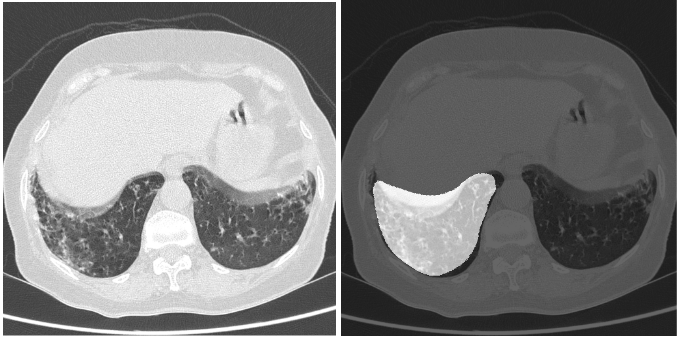

We tested our model using varied sets of data from different sources. We initially evaluated the model on our test set, consisting of 1330 images, in which COVID-19-positive samples had a prevalence of 20%. Our model gave a sensitivity of 0.963 (95% CI: 0.94-0.98) and a specificity of 0.936 (95% CI: 0.92-0.95). The dice coefficient on positive samples was 0.561. figures 2 and 3 show the superimposed masks on one of the slices.

Refer to caption

Figure 2: (Left) original image and (right) corresponding predicted mask.

Figure 3: (Left) original image and (right) corresponding predicted mask.